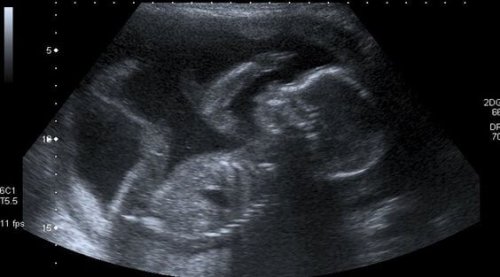

Eine Frau weiß, dass sie Mutter ist, wenn sie bei der ersten Ultraschalluntersuchung ihre Tränen nicht zurückhalten kann, wenn sie den Herzschlag ihres Kindes hört – ein Herz, das im Takt mir ihrem Herzen schlägt, das vor Freude hüpft und wenn sie die ersten Kindsbewegungen spürt.

Allerdings weiß diese Mutter, dass sie sich für den Moment und für mindestens neun Monate mit den Bildern begnügen muss, die der Ultraschall zeigt, um ihrem Kind ein Gesicht zu geben, sowie mit den subtilen Bewegungen des Babys, die nach und nach stärker werden.